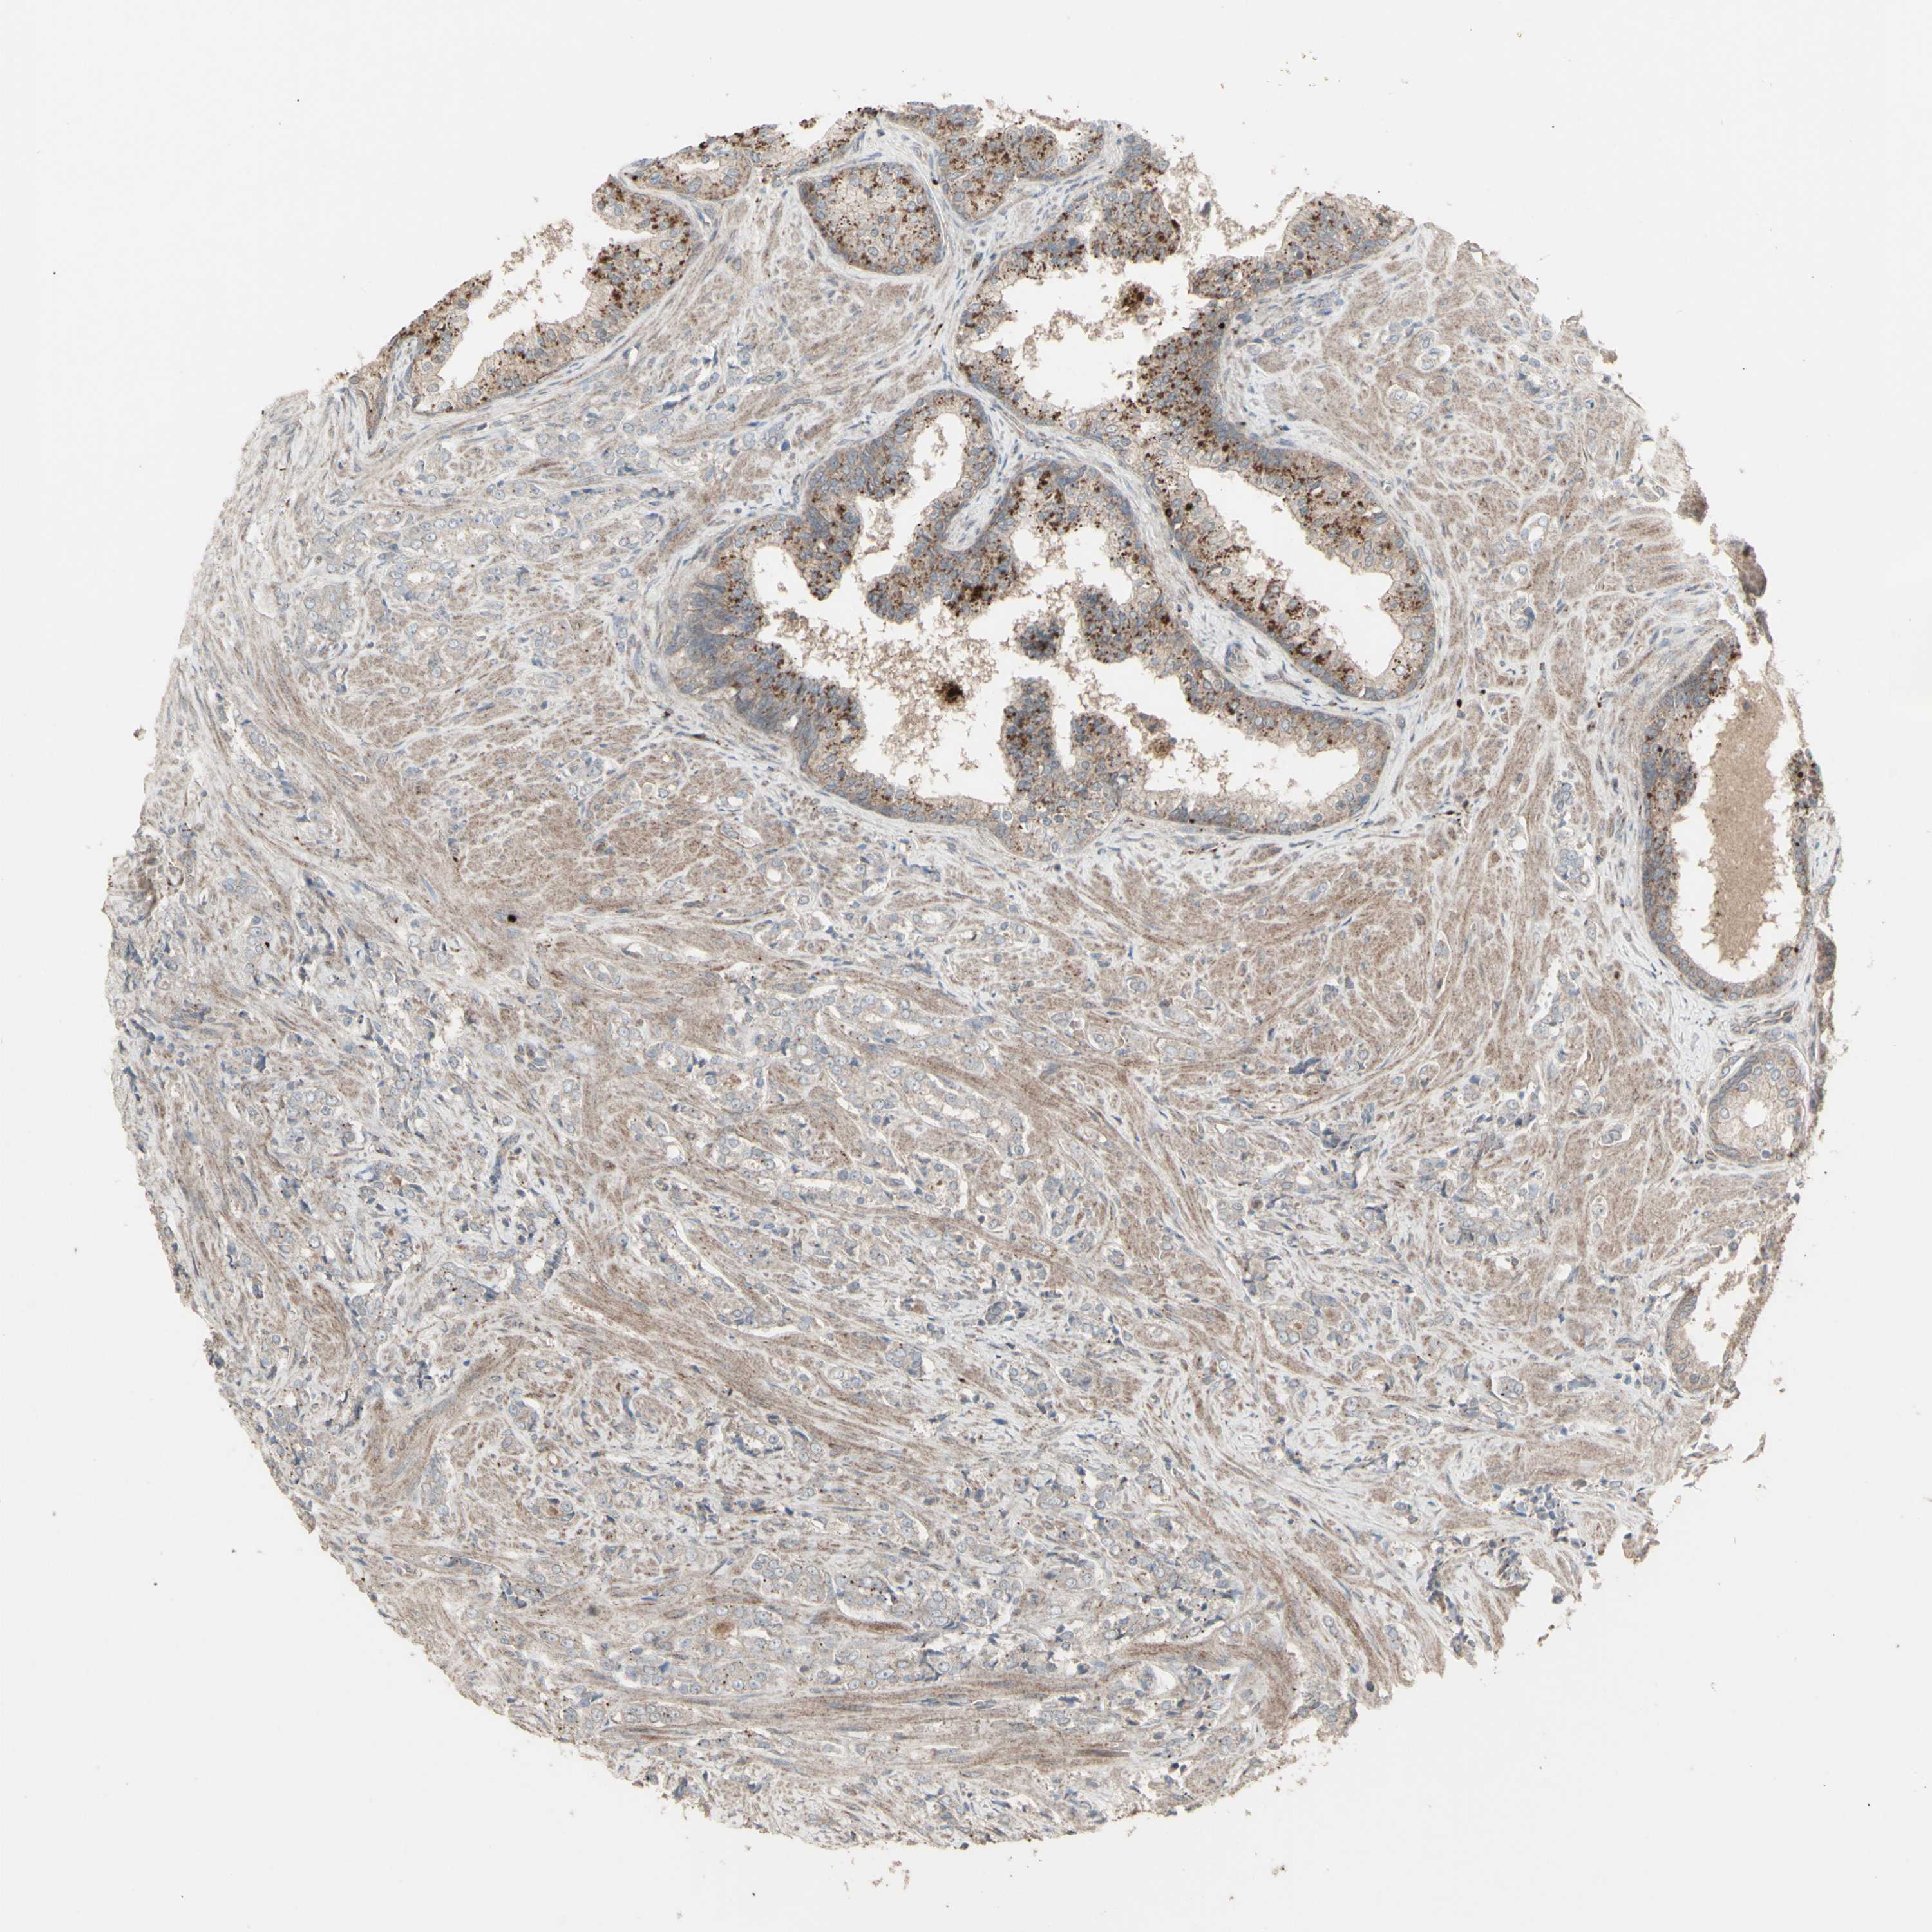

PROSTATE CANCER - Protein expressioni

A mouse-over function shows sample information and annotation data. Click on an image to view it in a full screen mode. Samples can be filtered based on level of antibody staining by selecting one or several of the following categories: high, medium, low and not detected. The assay and annotation is described here.

Antibody stainingi

Antibody staining in the annotated cell types in the current human tissue is reported as not detected, low, medium, or high, based on conventional immunohistochemistry profiling in selected tissues. This score is based on the combination of the staining intensity and fraction of stained cells.

Each image is clickable and will lead to virtual microscopy that enables deeper exploration of all samples and also displays staining intensity scores, fraction scores and subcellular localization as well as patient and tissue information for each sample.

Antibody HPA002633

Antibody HPA046758

Antibody CAB010906

Staining

High

Medium

Low

Not detected

Intensity

Strong

Moderate

Weak

Negative

Quantity

>75%

75%-25%

<25%

None

Location

Nuclear

Cytoplasmic/membranous

Cytoplasmic/membranous,nuclear

Adenocarcinoma, Medium grade

Adenocarcinoma, High grade

Adenocarcinoma, Low grade

Adenocarcinoma, NOS